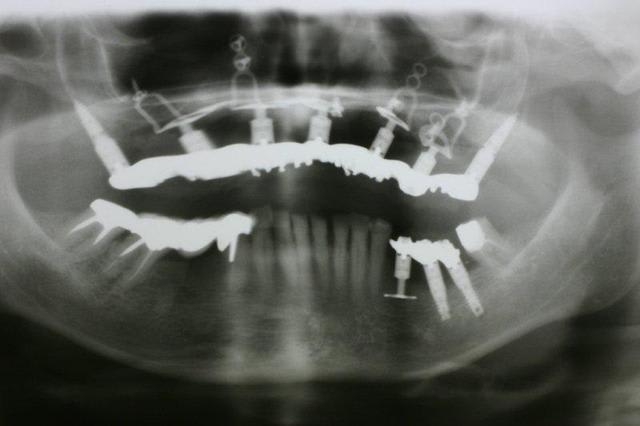

Les plaques existent depuis environ une dizaine d années

Je suis un des tous premiers à en avoir posé en dehors de GS puisqu à l époque il m en a confié une pour poser à la mandibule chez une patiente où je n avais pas pu poser un monodisk

J ai posé cette plaque en quais totalement enfoui à l époque : elle tjs là totalement indolore, bien sonore comme un cylindre

Je vais te filer qques photos d une patiente opérée voici 3 ans avec du nano et des plaques rien que l aspect de la muqueuse te montrera que tout ça est sain et ossifié

Merci, je me souviens bien de ce cas déjà présenté.

Le volume est en effet bien plus grand après, mais je me permet d'avoir quelques doutes sur l'intégration des plaques au niveau osseux...reste à avoir des études et des statistiques sur quelques centaines de cas, voir plus ;-)

Ben des études statistiques moi j en ai pas... J ai que mes propres cas

Par contre je peux te dire que les 4 plaques et même le monodisk sont sonores et parfaitement indolores donc a priori intégrés béton